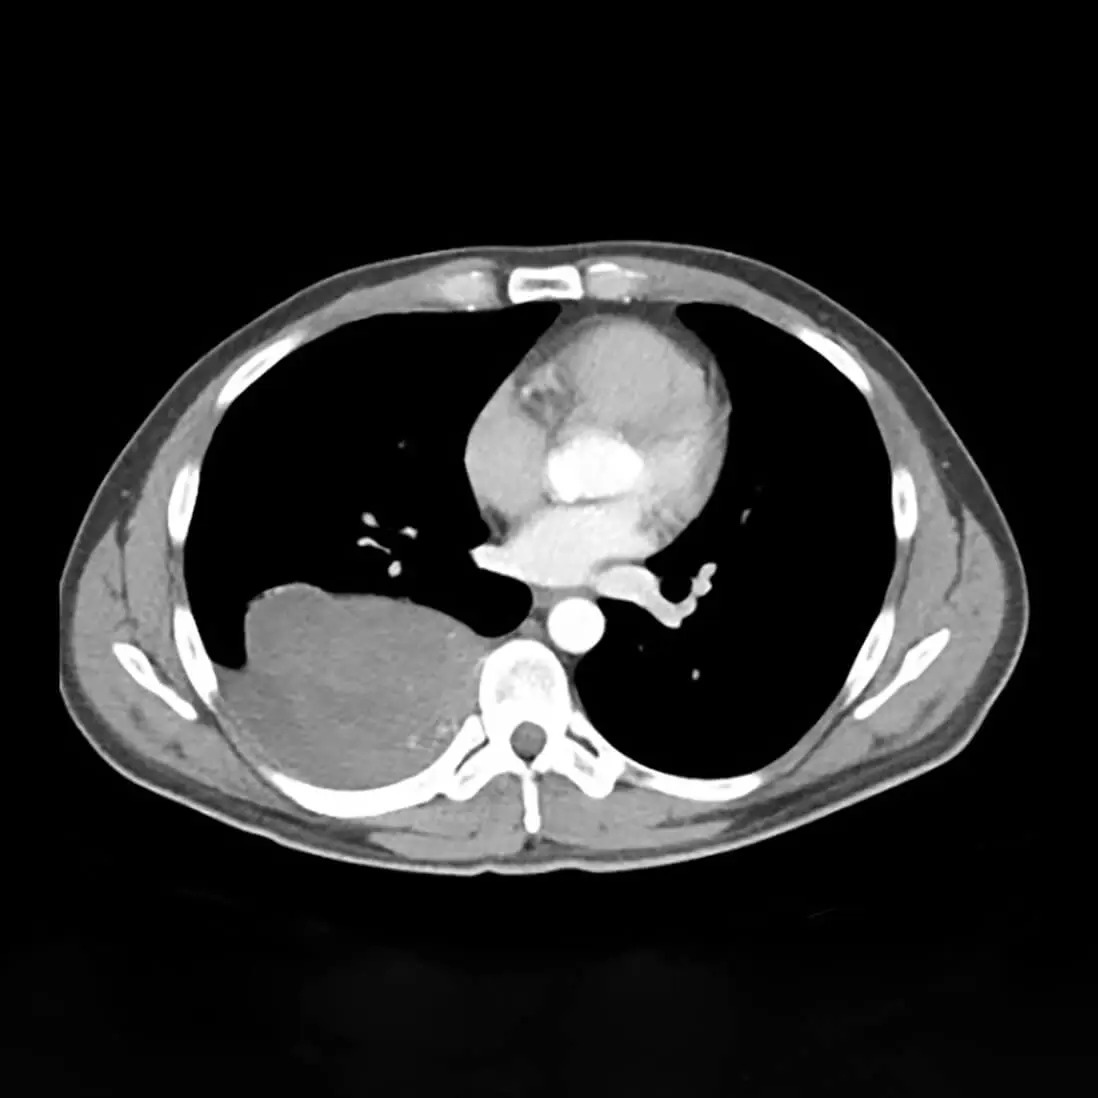

Η διερεύνηση περιλαμβάνει, εκτός από την αξονική τομογραφία θώρακος με ενδοφλέβιο σκιαγραφικό και μαγνητική τομογραφία θώρακος με ενδοφλέβιο σκιαγραφικό. Η μαγνητική τομογραφία διαφοροδιαγιγνώσκει συμπαγείς μάζες από κυστικές βλάβες.

Επιπλέον, παρέχει πληροφορίες για το αν ο όγκος εισβάλλει δια μέσου του σπονδυλικού τρήματος στο νωτιαίο κανάλι (όγκοι με μορφολογία κλεψύδρας). Το τελευταίο είναι ιδιαίτερα σημαντικό, καθώς στην περίπτωση αυτή, για την αφαίρεση του όγκου απαιτείται και συνεργασία με νευροχειρουργό.